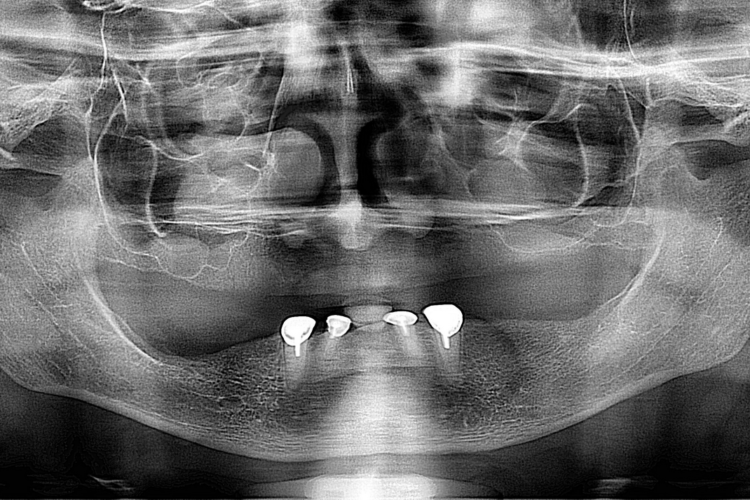

Pacienta in varsta de  65 ani, edentata total la maxilar si subtotal la mandibula la care s-a realizat o reabilitare protetica cu proteze mobile totale, la mandibula primind o supraproteza stabilizata pe magneti atasati unor cape pe dintii restanti. Protezele sunt armate cu plasa metalica individualizata pe forma crestelor restante pentru cresterea rezistentei mecanice a acestora.